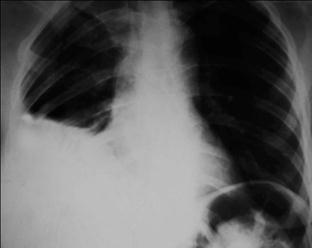

Рентгенологический признак пневмонии – инфильтративное, обычно одностороннее затемнение легочной ткани, которое может быть очаговым, сливным, сегментарным (рис.1-2), долевым (обычно гомогенным) и тотальным. Рентгенологическое исследование следует проводить в двух проекциях – задне-передней и боковой. При выполнении исследования следует оценить распространенность инфильтрации, наличие или отсутствие плеврального выпота и полости деструкции.

Рис. 1-2. Внебольничная сегментарная пневмония с локализацией в верхней доле правого легкого.